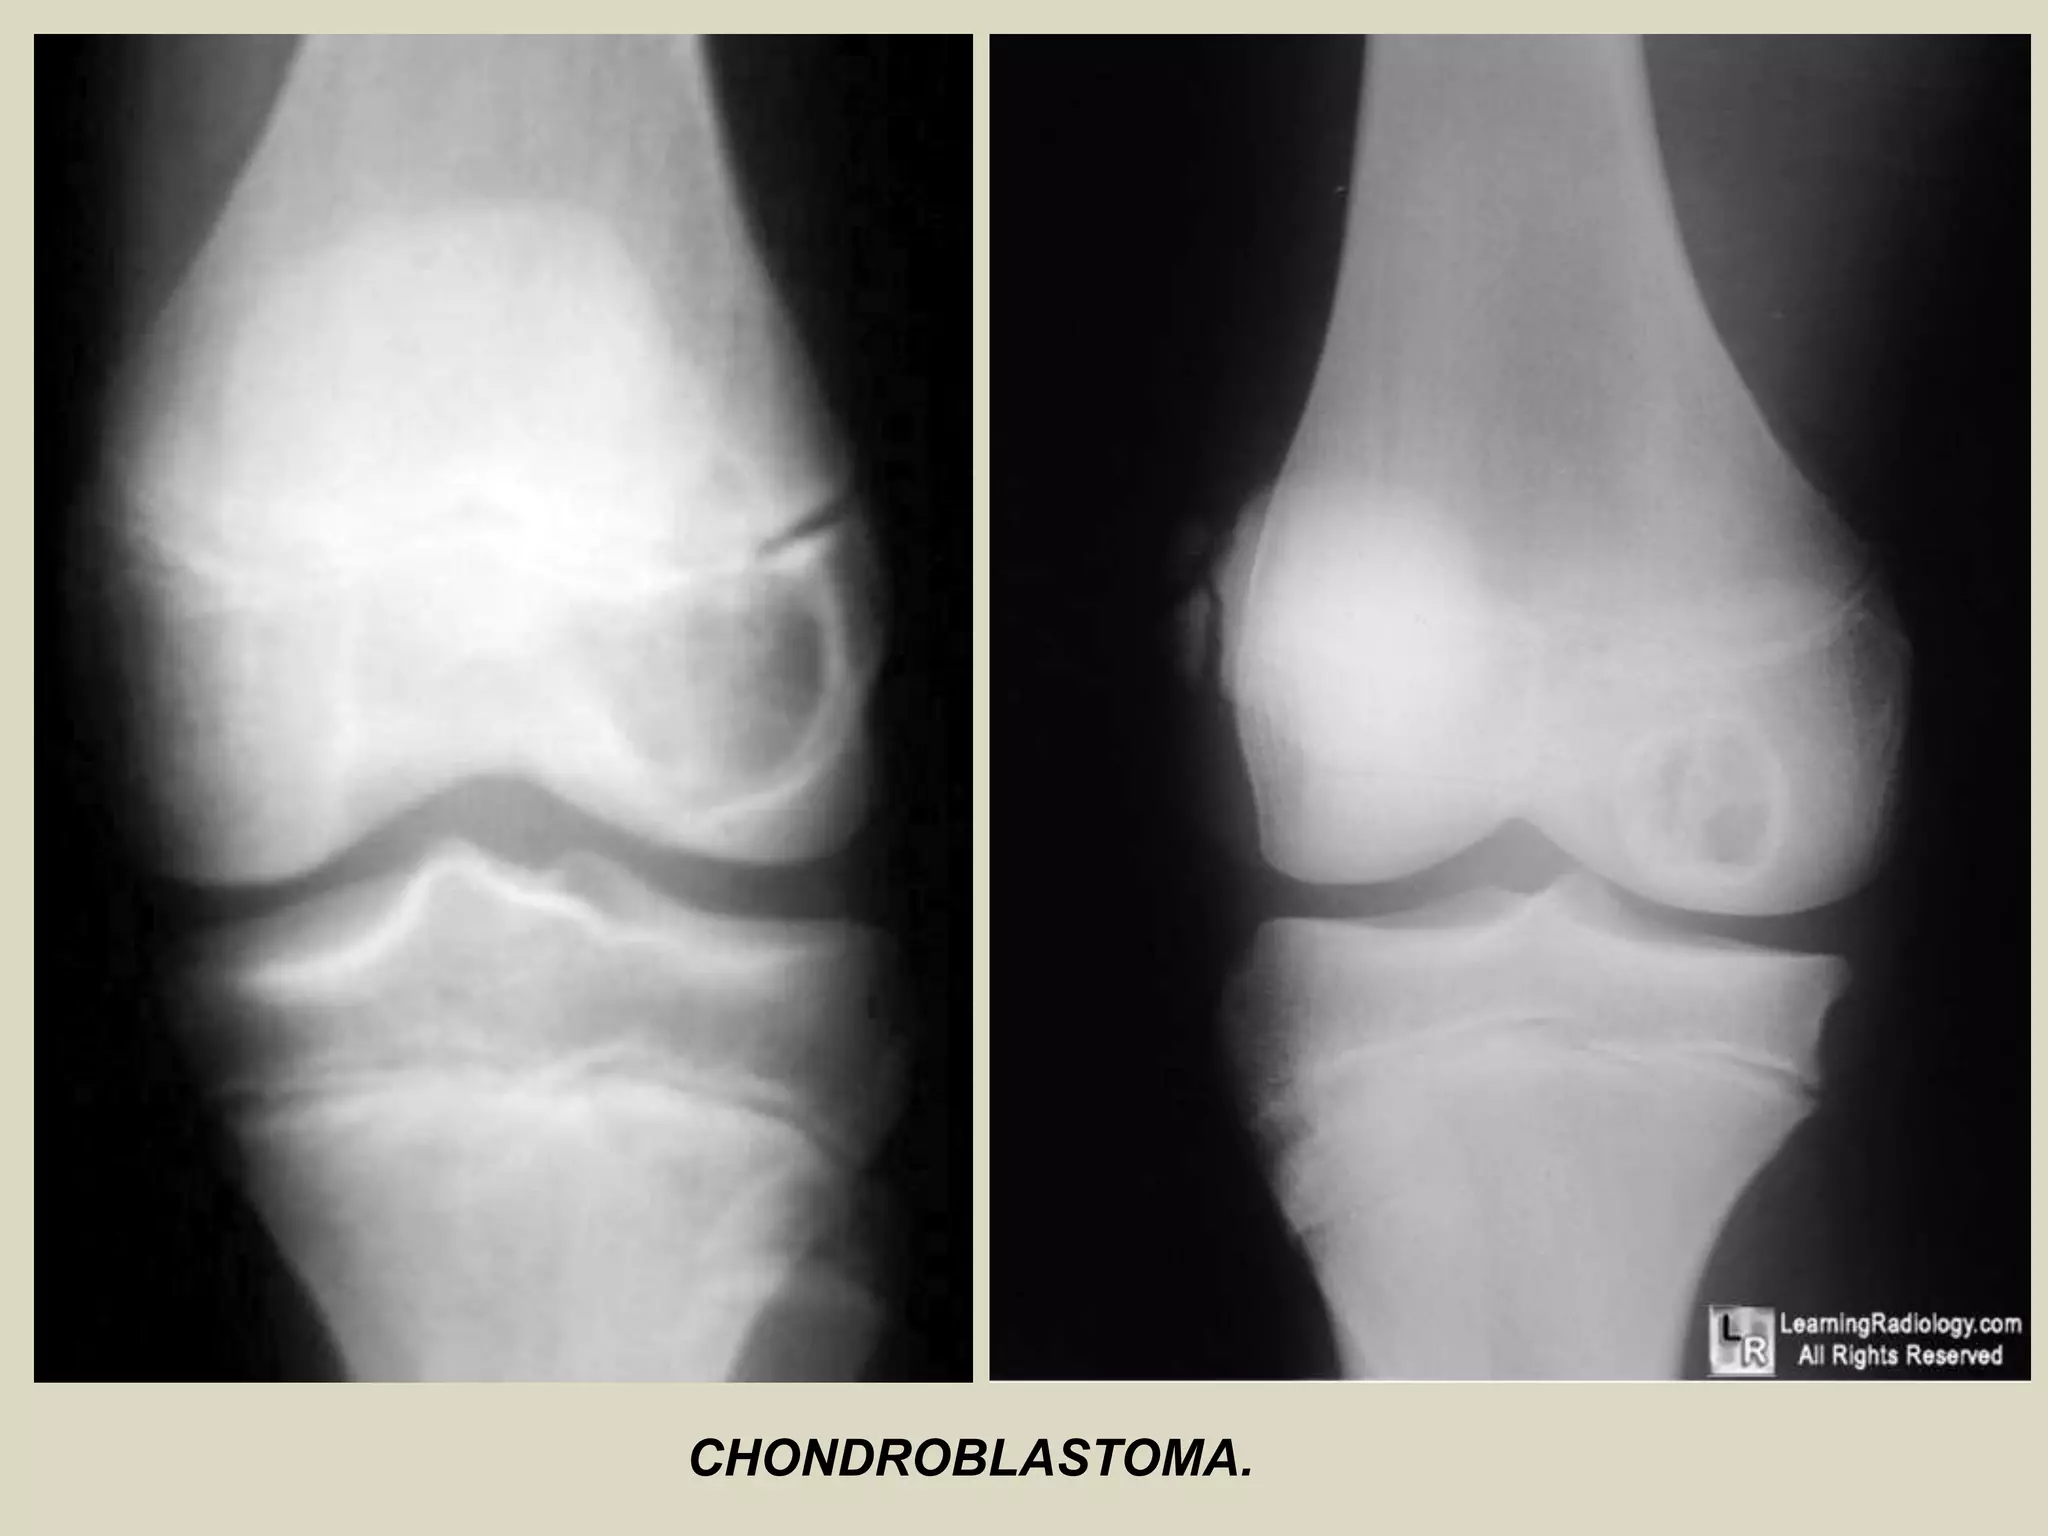

CHONDROBLASTOMA

Definition:

- Benign, cartilage producing neoplasm usually arising in the epiphyses of skeletally immature patients.

Epidemiology:

- Accounts for less than 1% of primary bone tumors.

- Most patients are between 10 and 25 years of age at diagnosis and there is a male predominance.

- Patients with skull and temporal bone involvement tend to present at an older age (40-50 years).

Sites of involvement:

- Usually arises in the epiphyses of the distal and proximal femur, followed by the proximal tibia

and proximal humerus.

- Patients with tumors arising in the flat bones, vertebrae and short tubular bones tend to be

older and skeletally mature, although rare cases have been reported in children.

Clinical findings:

- Majority of patients complain of localized pain, often mild, but sometimes of many years

duration.

- Soft tissue swelling, joint stiffness and limitation, and limp are reported less commonly.

- Minority of patients may develop joint effusion, especially around the knee.

Imaging:

- Typically lytic, centrally or eccentrically placed, relatively small lesions (3 to 6 cm), occupying

less than one half of the epiphysis.

- Shapely demarcated, with or without a thin sclerotic border.

- The presence of sclerotic rim, along with the younger age of the patient, helps to differentiate

chondroblastoma from giant cell tumor of bone, which generally lacks sclerotic border and occurs

in patients less than 20 years.

- Often helpful, matrix calcifications are only visible in about 1/3 of patients.

CHONDROBLASTOMA.

Chondroblastoma in the proximal tibia.